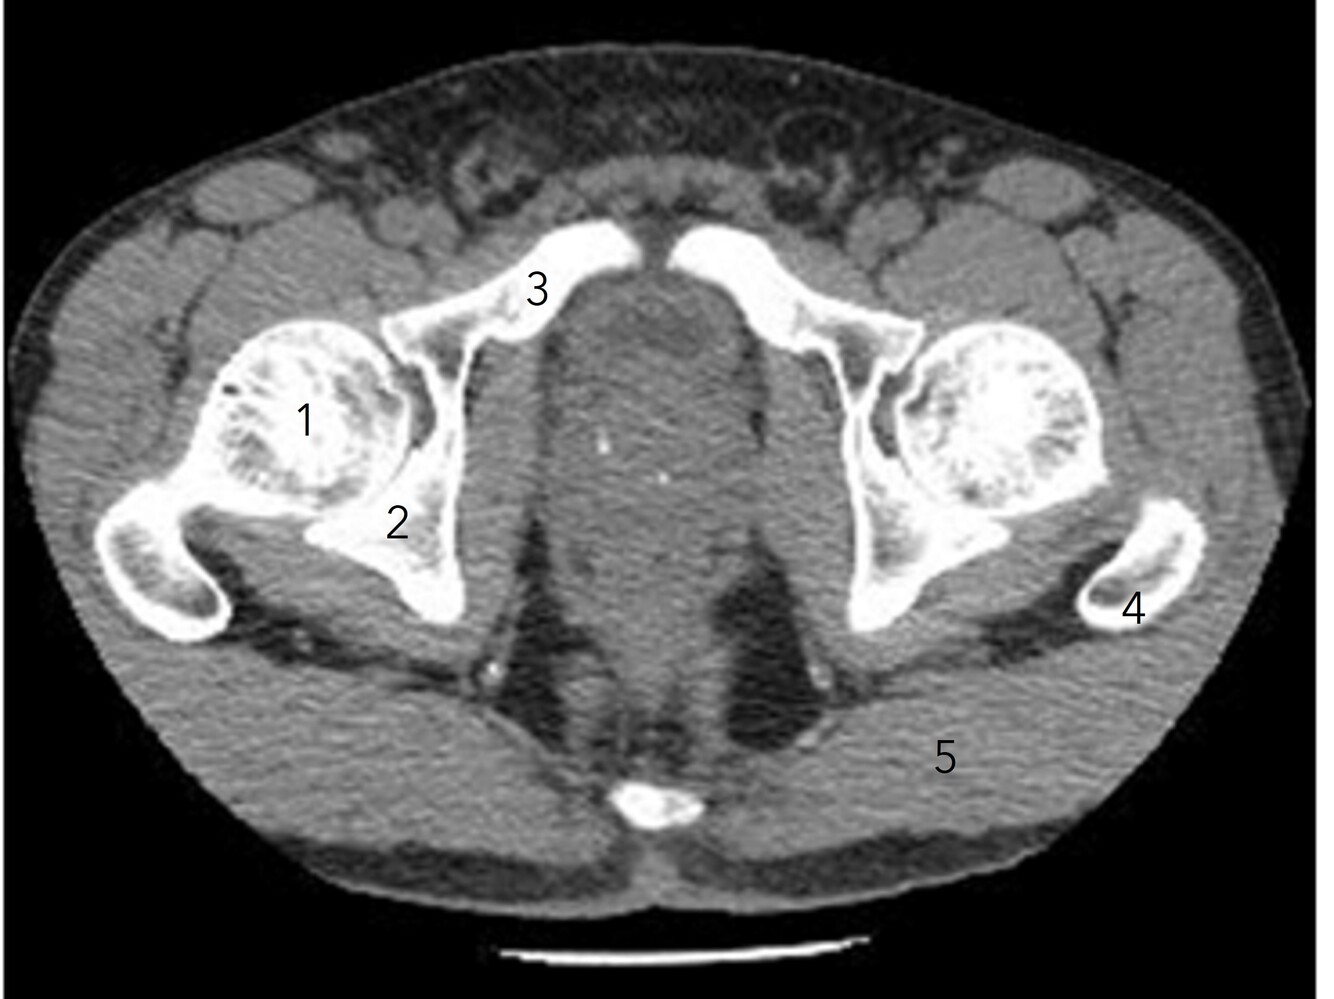

7

Q

Label 1-5

A

1. Rt femoral head

2. Rt ischium

3. Rt superior pubic ramus

4. Lt greater trochanter

5. Lt gluteus maximus